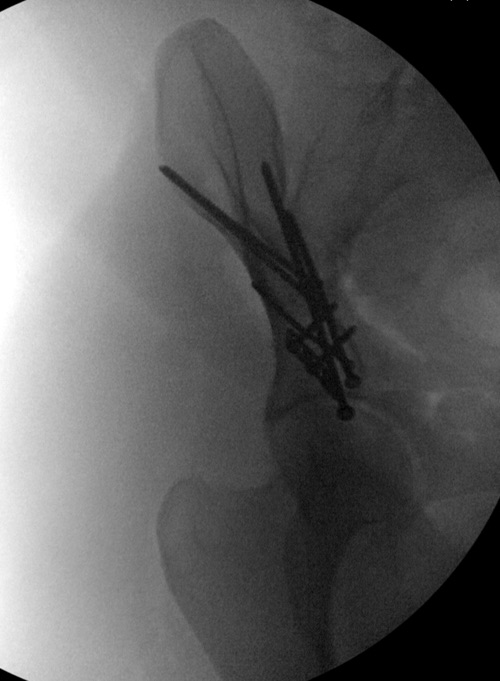

Это высокий перелом передней колонны вертлужной впадины (62A3.2).

Появились новые проекции. Да, это высокий перелом передней колонны левой вертлужной впадины со смещением.

Да, я понимаю, что предпочтительнее всего накостный синтез. Но если сравнивать АВФ с миниинвазивным, то ни тот ни другой не гарантируют 100%й репозиции. Перелом начинается с передней стенки впадины, идет вверх до крыла, а сзади спускаясь, останавливается едва достигнув задней колонны. Да, задняя колонна цела. Есть поперечные срезы КТ (сейчас показать не могу), где это четко видно. Перелом не завершенный. Учитывая этот факт, я и подумал о возможности АВФ. Простите мне мою упрямость)).

Данная картина показывает очень редкий перелом передней колонны, но перед операцией еще раз надо просмотреть обещанные дополнительные КТ срезы.